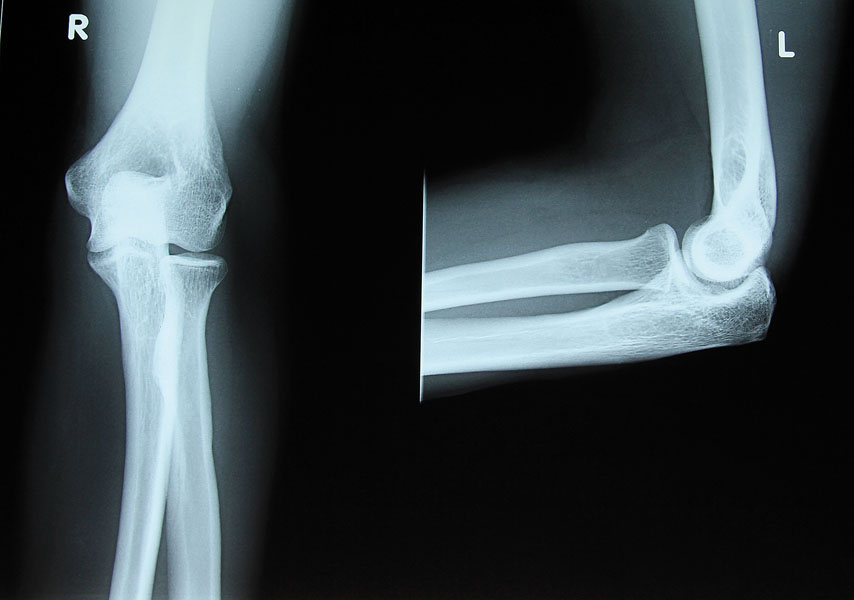

Obecnie urazy więzadłowe, łąkotek i struktur kostnych kolana stanowią razem około 30-40 % wszystkich urazów narciarskich. Początkowo najczęstszymi urazami w narciarstwie były urazy kończyn dolnych (złamania kostek i goleni, skręcenia stawu skokowego). Zmieniło się to w następstwie rozwóju sprzętu narciarskiego, szczególnie wiązań i butów narciarskich, które teraz automatycznie uwalniają nogę narciarza, gdy działają na nią zbyt duże siły. Niestety, nowe rozwiązania nie dały ochrony kolanom. Skręcenie więzadła pobocznego przyśrodkowego, więzadła krzyżowego przedniego (ACL), złamanie głowy kości piszczelowej i urazy łąkotki są obecnie największym zagrożeniem dla miłośników białego szaleństwa.